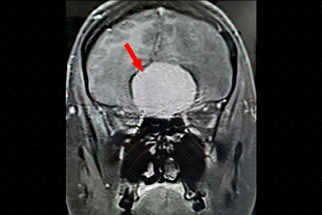

Texto alternativo para a imagem Figura 2. Créditos: Dra. Elazir Mota - Rio de Janeiro/RJ

Descrição da figura 2: Lesão do mesmo paciente na sequência T2 também apresentando marcado hipossinal/isossinal quando comparado ao córtex adjacente. Observe o edema circunjacente (imagem com marcado hiperssinal no T2).